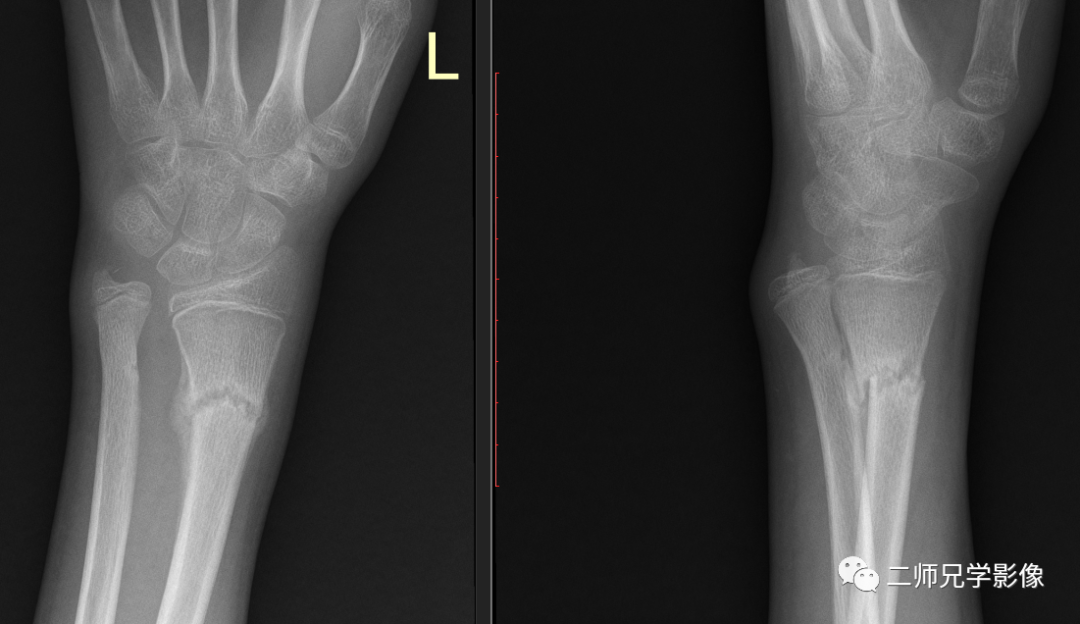

病例一:小朋友左尺桡骨远端骨折复查,申请单:左腕关节正侧位

怎么取放射片放射拍片中的“几何学”,临床医生和技师都掌握了吗?_https://www.jmylbn.com_新闻资讯_第10张

左尺桡骨远端骨折,局部骨痂形成,断端对位良好